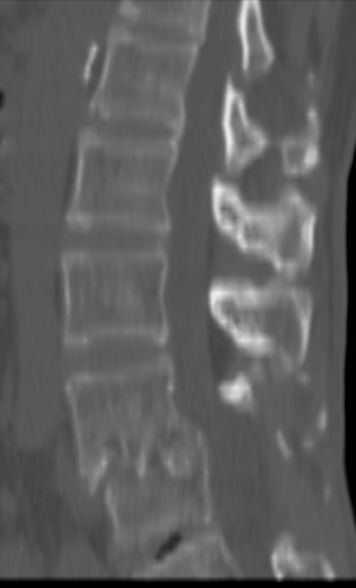

以下是引用余辉在2007-9-4 21:00:00的发言:[br]椎体棘突有点异常(像是被切割了),不知有否手术史,如椎体融合术等。单纯的退行性变可以出现椎间隙变窄,但同时一般会出现椎体上下缘的硬化增生,且椎体间完全融合的机率更小,本例椎体完全融合且椎体上下皮质缘破坏掉了,如果没有手术史,就应该考虑椎间盘炎性病变了,且椎体棘突及棘间韧带的变化也并不是不支持这个,多数小关节也融合了,且其形态也容易让人联想到如强脊炎及类风关等病变。[br][br][本贴已被 余辉 于 2007-9-4 21:03:55 修改过]

以下是引用chry3在2007-9-4 20:42:00的发言:[br]椎间盘病史?是什么样的病史,无双下肢放射痛,那就不是椎间盘突出了。是感染、什么性质的?[br]从图象看椎间隙消失,椎间盘组织未见,锥体滑脱是因为椎间盘溶解造成的[br]l4、5椎体骨质结构未见异常,l5上缘是l4的长期压迫所致[br]还是考虑椎间盘感染,结核。[br]